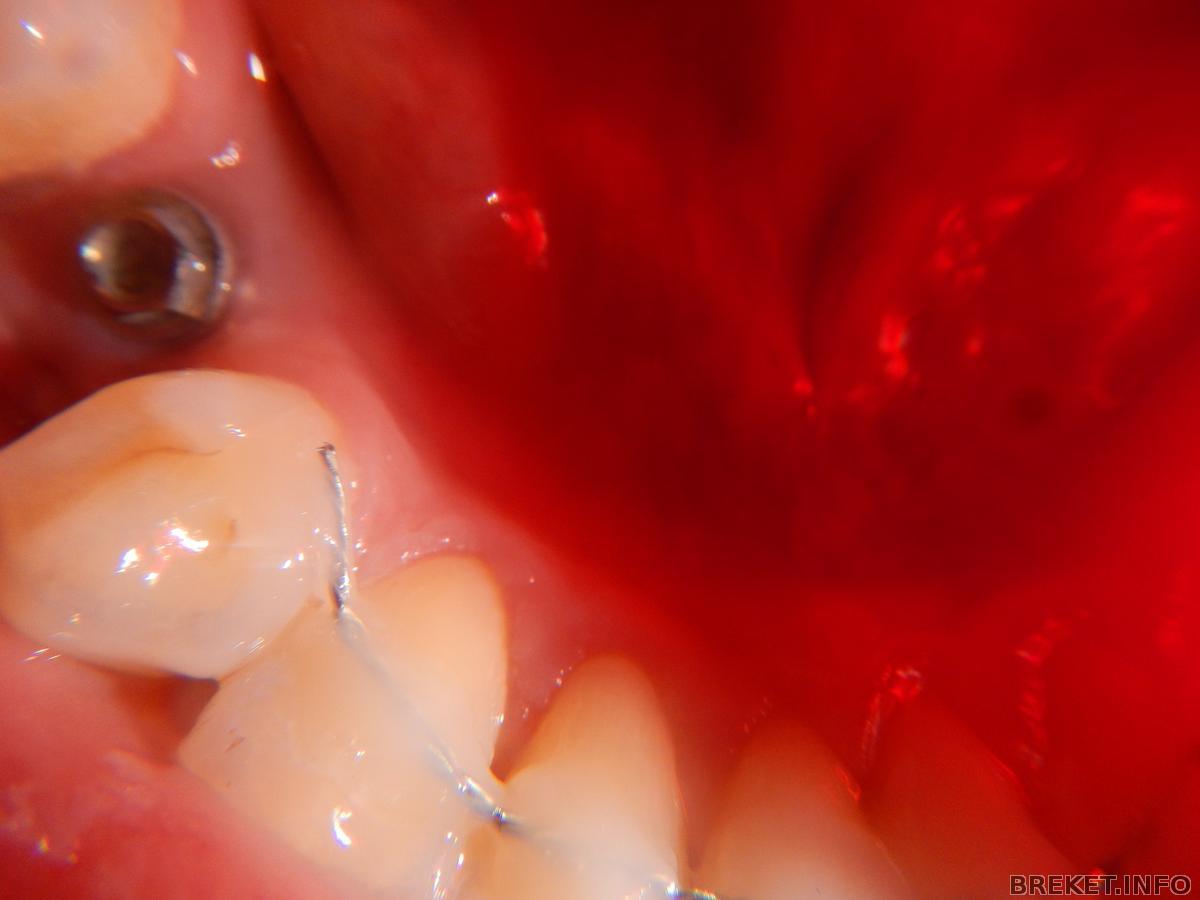

Да, там уже импланты вкручены(железяка торчит), на днях к имплантологу за зубами

Leka89 имплантация у меня была одновременно с удалением сложнй 8. прошла нормально, достаточно быстро. Опухоль была не большая с одной стороны, а со стороны зуба выдернутого с недельку держалась. Боятся особо нечего.приятного конечно мало, но ради результата. Все манипуляции у меня были зашиты, зажило все хорошо, сейчас и не видно, просто железки торчат(как будто всегда там были). На днях иду к имплантологу(наверно слепки сначала) я не знаю. прошло 3 месяца к слову.

"И главное, за какое время до снятия БС это происходило? "- Мне моя ортофея сама сказала, что пора выдирать 8 и на консультацию к имплантологу-я все это очень быстро сделала, а имплантолог тоже тянуть не стал.

импланты ставят в конце за 3-4 мес до снятия.(как мне объяснили) ну вот и вышло,что импланты, вместе с БС сейчас перез самими зубами сняли низ, тк слепки с брекетами не сделать. ну и потом верх подгонят под зубы и снимут.